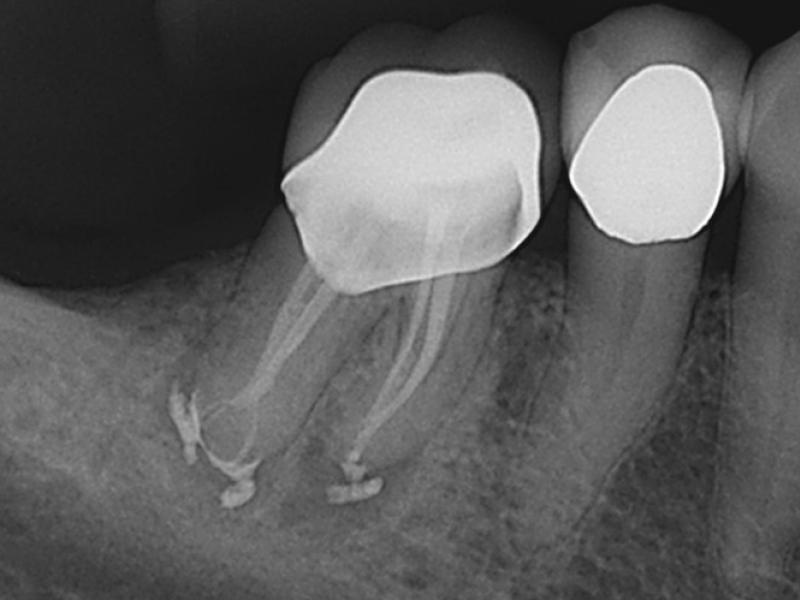

Middle Mesials in MN Molars

Karen S. Potter, DDS

View Case Images